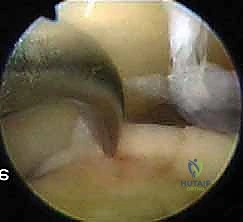

2. Diagnostic Arthroscopy and Lesion Characterization

Now that we're in, let's perform a systematic diagnostic arthroscopy.

* Initial Survey: Systematically visualize the entire joint: the tibial plafond, medial and lateral gutters, talar dome, and the anterior and posterior aspects of the joint. Look for synovitis, loose bodies, impingement lesions (soft tissue or bony), and any associated pathology.

* Locating the OLT: Our preoperative MRI indicated a medial talar dome lesion. We'll use a probing hook to precisely locate and characterize it.

* Assess the size (length and width).

* Evaluate the depth of the cartilage defect.

* Determine the stability of the surrounding cartilage and the lesion itself. Use the probe to gently push on the lesion. Is it soft? Is it delaminated? Is there an intact cartilage surface over a subchondral cyst?

* Our current patient has a Stage III lesion, meaning the articular cartilage is breached, and we expect to find synovial fluid between the fragment and the underlying subchondral bone. This is ideal for microfracture.